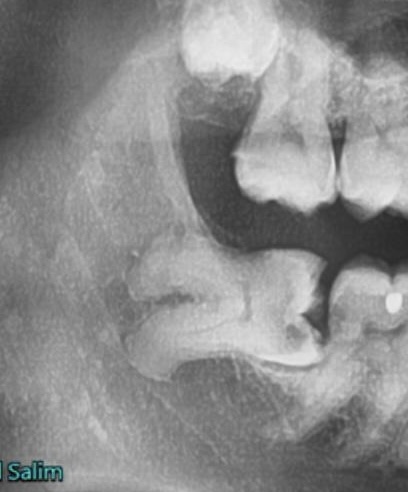

A dental X-ray showing teeth and jawbone structure.